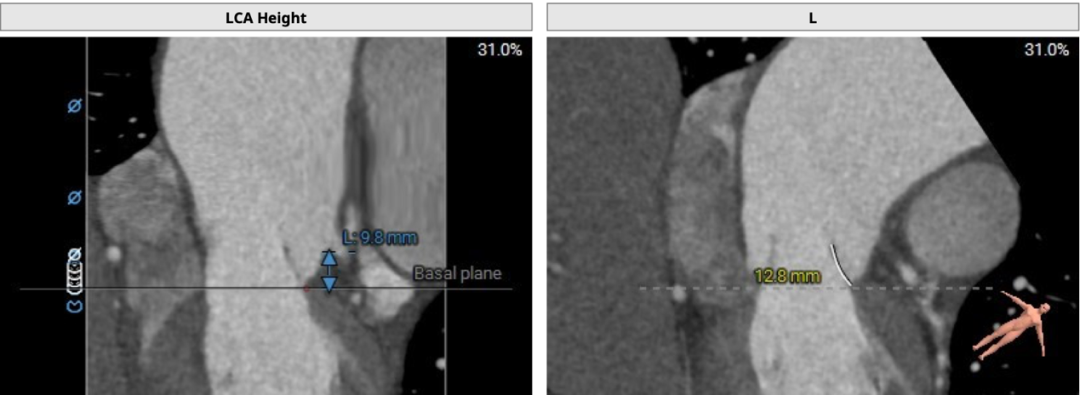

左侧冠脉开口高度低,LCA 9.8mm,左冠瓣瓣叶长度约12.8mm;右侧冠脉开口高度可,RCA 14.3mm:

术中建议造影角度RAO 7°,CAU 14°(其它参考角度如下图):